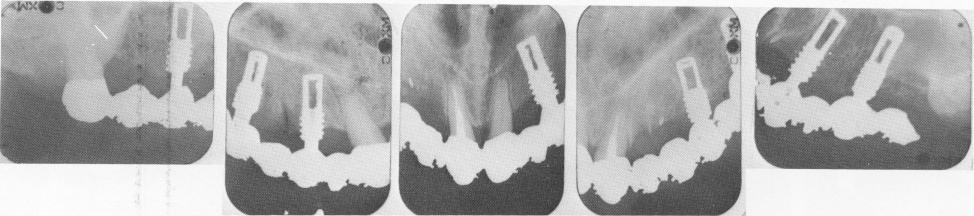

Fig. 5-43. Linkow's self-tapping vent-plant, shown in numerous variations for almost any bone situation. Those on the far left, for example, are used for shallow alveolar bone.

Fig. 5-44. Excellent bone regrowth is seen around the deeper portions of this 6-year postoperative early model vent-plant, a non–self-tapping implant made of tantalum. Later changes moved the widest portion apically to make room for a thinner solid shaft. (From Linkow, L. I.: Maxillary endosseous implants, Dent. Concepts 10:14-24, 1966.)